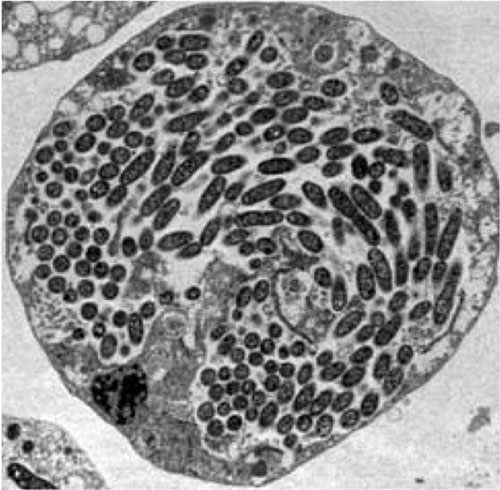

Section G. Figure 4. Transmission electron micrograph of an amoeba-filled with Legionella pneumophila.